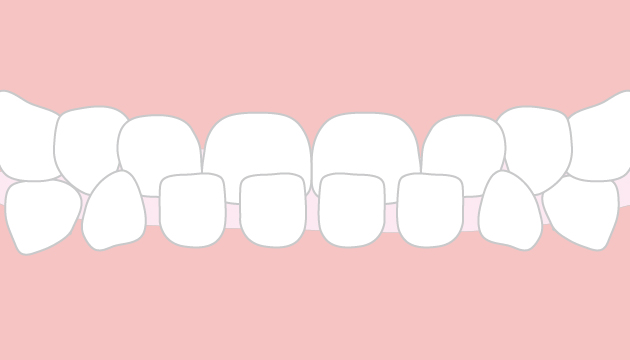

【同梱不可】 受け口【反対咬合】 アントン矯正歯科クリニック | 臨床医学